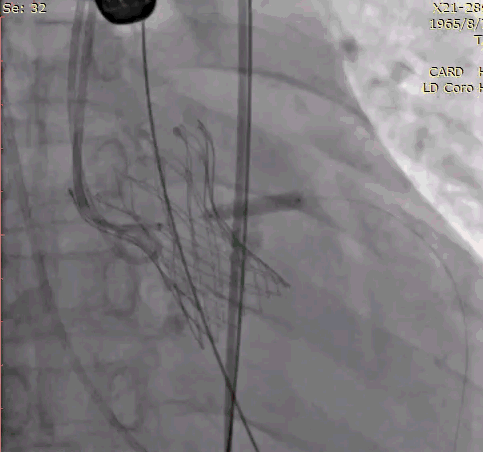

手术影像记录:

植入前冠脉造影

主动脉根部造影

直头导丝跨瓣

20mm球囊预扩

冠脉保护支架植入

AV23瓣膜释放到工作位

瓣膜完全释放

冠脉支架释放

植入后造影